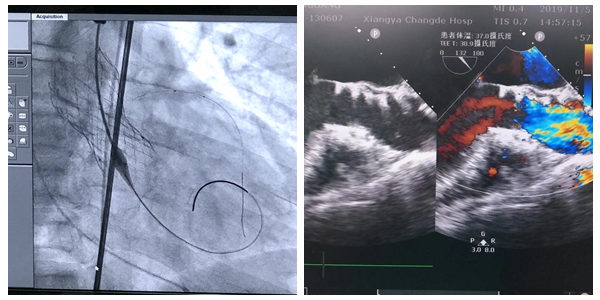

为此,心胸外科联合心血管内科、麻醉手术室部、ICU、超声影像科、放射介入科、放射影像科等多个相关科室组成的TAVI团队进行了多学科会诊,确定行介入手术。通过周密的术前准备,11月5日,TAVI团队在心脏介入室为刘某实施了微创介入经股动脉主动脉瓣置入术,折叠的人工主动脉瓣经过细小的管状输送系统经过心尖,精确到达主动脉瓣,瓣膜支架慢慢张开。仅一个小时的手术时间,让这位主动脉瓣狭窄并关闭不全的患者获得了“心生”。术中刘某各项生命体征平稳,术后第二天便已下地自主行走。复查其造影瓣膜位置良好,经食道心脏超声主动脉瓣未见返流,冠状动脉血流状况良好。